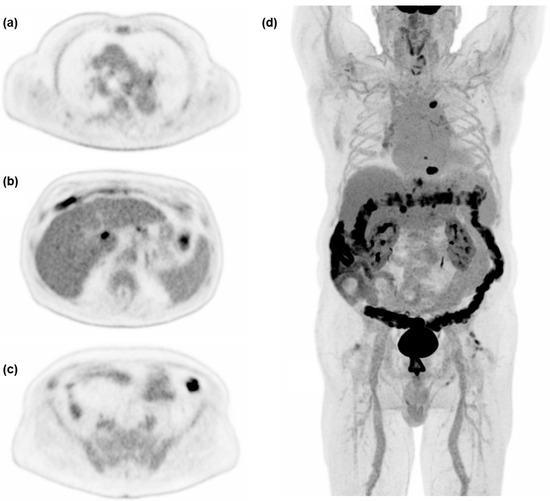

One patient out of 50 had a 30 mm rather than 60 mm VOI placed in the right liver lobe due to wide-spread disease and major vessels. Image noise computed as COV was closest to current acceptable values for standard of care after 90 s on the Vision Quadra (COVmean = 0.14). Therefore, 90 s acquisition was implemented as the reference acquisition for current clinical standard in PET/CT in this study. As expected, COV improved significantly with increasing acquisition time across all time points (PB < 0.001). Axial slices and MIP as viewed by observers in the qualitative evaluation can be seen in Figure 3.

Figure 3. Examples of axial slices and maximum intensity projection (MIP) at 600 s acquisition time, used for the qualitative evaluation of image quality in a 75 y male referred for treatment control of hepatocellular carcinoma. (a) Level of the carina of the trachea, (b) level of simultaneous display of liver, ventricle, and spleen, (c) level of the common iliac artery bifurcation, (d) MIP.